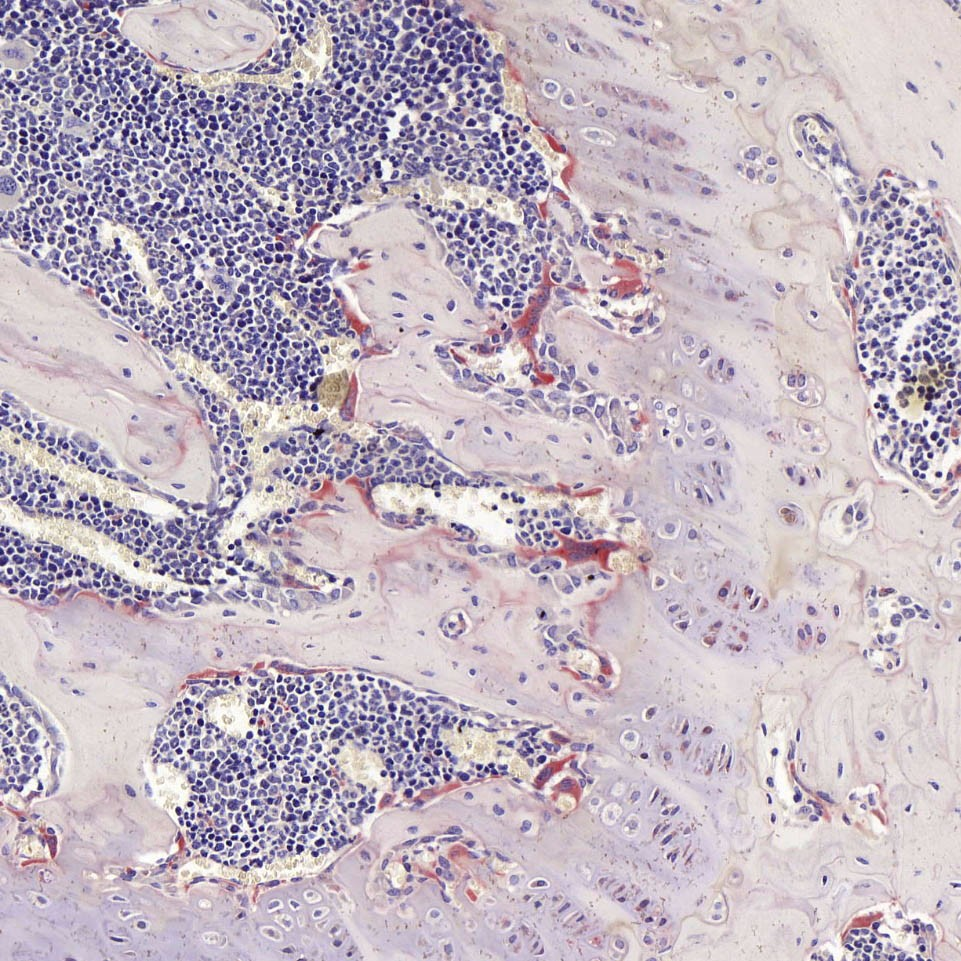

抗酒石酸酸性磷酸酶染色,又称Trap染色,是用于检测骨、骨细胞中破骨细胞的染色,使破骨细胞呈红色,细胞核浅蓝色, 用以显示破骨细胞的分布及数量变化。

Trap染色是用于检测骨组织、骨细胞中特征物质的染色,使破骨细胞呈红色,背景呈绿色或蓝色。抗酒石酸酸性磷酸酶 (Trap)为破骨细胞的标志酶,特异地分布于破骨细胞中,为破骨细胞所特有,通常作为鉴别破骨细胞的重要标志物。在含 酒石酸的酸性条件下,trap能将萘酚AS-BI磷酸盐水解,产生的萘酚AS-BI立即与fast red或六偶氮副品红结合,在酶活性部 位形成不溶性的红色染料,通过观察红色染料的形成可间接了解酸性磷酸酶的活性,进一步鉴别及分析破骨细胞的状态。

破骨细胞呈酒红色或浅红色,细胞核呈浅蓝色